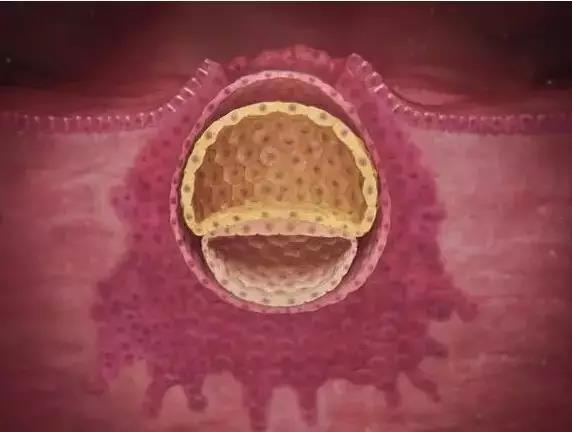

3周

这个集聚了成百上千个

快速繁殖的细胞的球称为囊胚

囊胚依偎在子宫内营养最丰富的地方